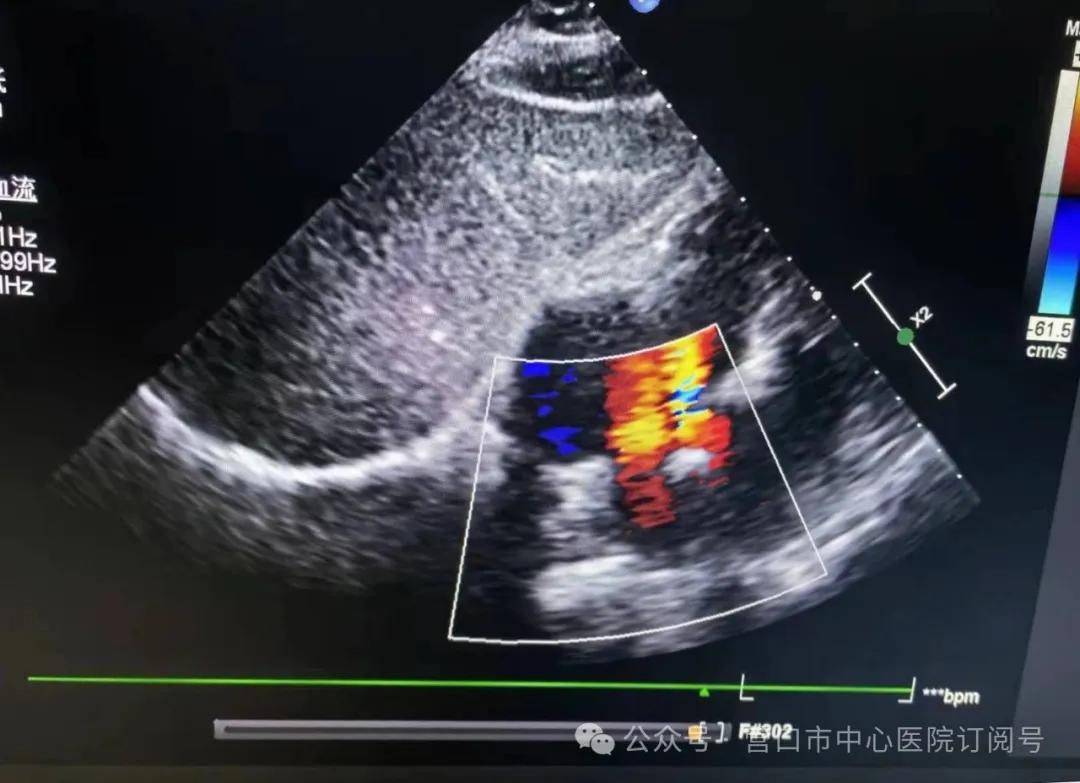

中年女患,因“胸闷、气短5年,加重半个月”就诊,完善心脏超声确诊先天性心脏病房间隔缺损,缺损较大,直径达18mm,并且已经导致右心显著增大(图1)。经过多学科会诊,并与超声科主任反复沟通,充分术前讨论及评估,考虑患者可以实施介入封堵治疗,无需外科开胸手术。在周密的术前准备后,为患者实施房间隔缺损介入封堵治疗。整个团队密切配合、精准操作,手术用时仅约半小时,就将缺损部位完美堵住。术后24小时复查心脏彩超证实完全封堵,无残余漏,且未影响房室瓣活动及上、下腔静脉回流,右房及右室均明显缩小,右房从41*47mm降至35*45mm,右室大小从37mm降至17mm,效果显著(图2、3)。患者术后第1天离床活动,术后3天出院,恢复良好。

图2 胸骨旁四腔心切面可见封堵器固定牢靠,未见残余分流